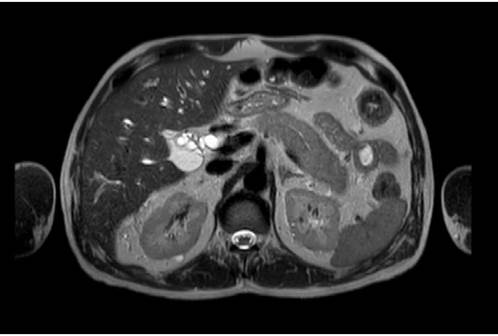

In view of these findings, the patient was admitted to the hospital and during his first day of stay he was assessed by the general surgery department, which considered that he presented hyperbilirubinemia of obstructive pattern with a lesion in the head of the pancreas. So, CT and MRI scans of the abdomen were requested, as well as tests for tumor markers. The test results were available on the following day and reported negative tumor markers (CA 19-9: 14.5 U/mL, alpha-fetoprotein: 2.46 ng/mL, and carcinoembryonic antigen: 2.19 ng/mL). The MRI showed a diffuse alteration in the morphology of the pancreas, with enlargement and obstruction of both the bile duct and the pancreatic duct (without dilatation) (Figure 1). Finally, the CT scan showed an alteration of the peripancreatic fat that formed a low-density "halo" sign and suggested AIP as the main differential diagnosis (Figure 2). Considering these findings, during the third day of hospital stay, the general surgery service considered ruling out an inflammatory process, and in view of a possible autoimmune etiology, requested immunoglobulin blood tests.

Magnetic resonance imaging of the abdomen showing alteration of the pancreatic morphology with enlargement and loss of lobularity.

Figure 1: Magnetic resonance imaging of the abdomen showing alteration of the pancreatic morphology with enlargement and loss of lobularity.

Source: Image obtained while conducting the study.

In the present case, the patient was diagnosed with AIP since both CT and MRI scans showed a diffuse alteration of the pancreatic morphology, an enlargement of the pancreas and an obstruction of the bile duct and pancreatic duct (suggesting narrowing of these organs), with no findings of proximal dilatation, which are characteristic imaging findings of this condition.1,2